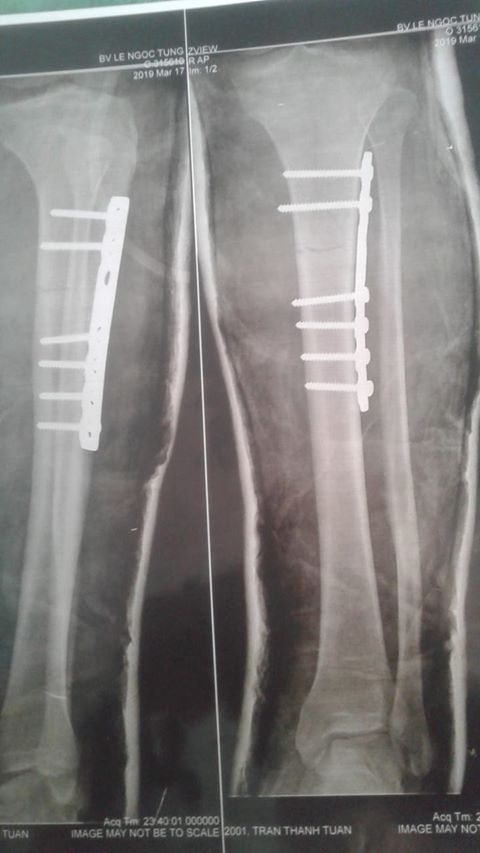

| Ảnh chụp vết thương của người lao động |

Ngày 20/2/2019, tôi được nhận vào làm việc tại Công ty TNHH Tư vấn thiết kế cơ khí xây dựng Khang Triết, dạng hợp đồng thử việc, thỏa thuận miệng. Đến ngày 17/3/2019, trong quá trình vận chuyển vật liệu (các thanh thép 12ly, dài khoảng hơn 12m) thì xảy ra tai nạn khiến chân phải bị gãy, phải vào Bệnh viện Đa khoa Lê Ngọc Tùng (TP. Tây Ninh, tỉnh Tây Ninh) phẫu thuật.

Trong quá trình điều trị tại Bệnh viện Đa khoa Lê Ngọc Tùng, tôi được phẫu thuật đóng đinh cố định, đến ngày 21/3/2019 được ra viện và yêu cầu tái khám theo chỉ định của bệnh viện. Tuy nhiên, hiện tại phía Công ty TNHH Tư vấn thiết kế cơ khí xây dựng Khang Triết chỉ thanh toán tiền viện đến hết ngày 21/3/2019 cho tôi và nói rằng công ty đã hết trách nhiệm, việc điều trị lần sau do cá nhân tôi phải tự lo liệu, công ty cũng thông báo việc bằng miệng việc đơn phương chấm dứt hợp đồng lao động với tôi.